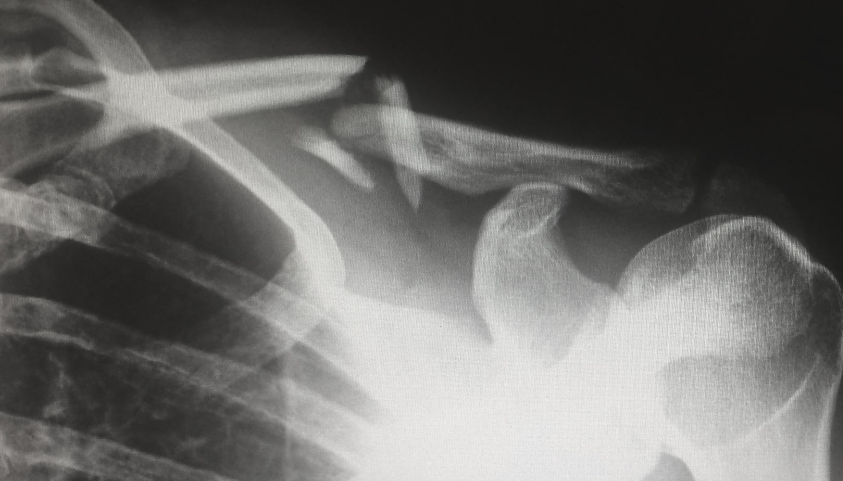

一直以來(lái),醫(yī)療器械領(lǐng)域都是海外大藥廠占主導(dǎo)地位。如下圖所示,2019年國(guó)內(nèi)脊柱類植入器械市場(chǎng),占據(jù)主導(dǎo)地位的強(qiáng)生和美敦力市場(chǎng)份額超過(guò)50%。

國(guó)產(chǎn)品牌領(lǐng)頭羊威高骨科的市場(chǎng)份額不過(guò)7.92%,排名第二的三友醫(yī)療市場(chǎng)份額更是不到4%,與巨頭們的差距存在明顯差距。